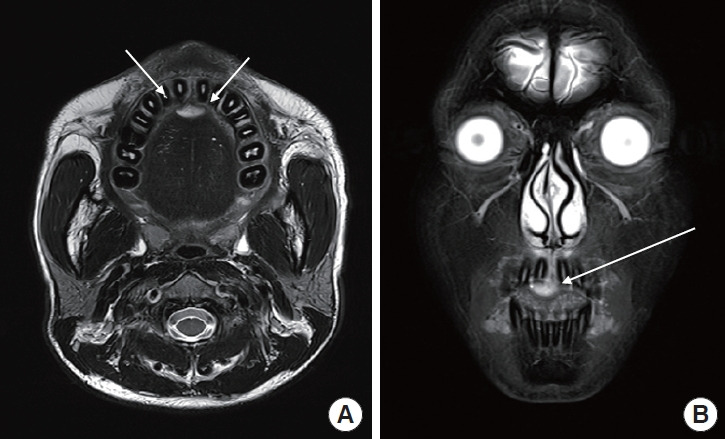

This case report describes a rare occurrence of pyogenic granuloma (PG) in the hard palate deviating from its typical gingival location that led to the formation of an alveolar cleft. The aggressive growth pattern of the lesion, with atypical progression from a pedunculated nodule to an alveolar cleft, raised concern. The diagnosis was based on magnetic resonance imaging and computed tomography findings, which revealed a tadpole-shaped lesion originating from the midline hard palate. The differential diagnosis included a minor salivary gland tumor. Surgical excision was performed under general anesthesia and resulted in a mucosal defect without nasolabial fistula formation or bone exposure. The palatal defect was packed with oxidized regenerated cellulose and closed with Vicryl Rapide sutures, both of which contributed to the patient's successful outcomes. Our comprehensive approach, extending across the stages of surgical planning, execution, and postoperative care, demonstrated the advantages of a multidisciplinary strategy for the accurate diagnosis and effective treatment of palatal PGs. This report makes a meaningful contribution to the existing literature on common oral lesions by emphasizing the importance of a broad differential diagnosis and a systematic approach to oral pathologies. It also raises clinical awareness of PGs with atypical presentations and the diagnostic challenge that they pose.

本病例报告描述了一起罕见的硬腭化脓性肉芽肿(PG)病例,该病例偏离了其典型的牙龈位置,导致牙槽裂的形成。病变的侵袭性生长模式,以及从蒂状结节到齿槽裂的非典型进展,引起了人们的关注。诊断依据是磁共振成像和计算机断层扫描结果,结果显示病变呈蝌蚪状,起源于硬腭中线。鉴别诊断包括轻微的唾液腺肿瘤。手术切除是在全身麻醉的情况下进行的,术后出现了粘膜缺损,但没有形成鼻唇瘘或骨头暴露。腭部缺损处用氧化再生纤维素填塞,并用 Vicryl Rapide 缝线缝合,这两种方法都有助于患者取得成功。我们的综合方法贯穿了手术计划、实施和术后护理的各个阶段,证明了多学科策略在准确诊断和有效治疗腭PG方面的优势。本报告强调了广泛鉴别诊断和系统治疗口腔病变的重要性,为现有的常见口腔病变文献做出了有意义的贡献。它还提高了临床对表现不典型的腭咽癌及其诊断挑战的认识。